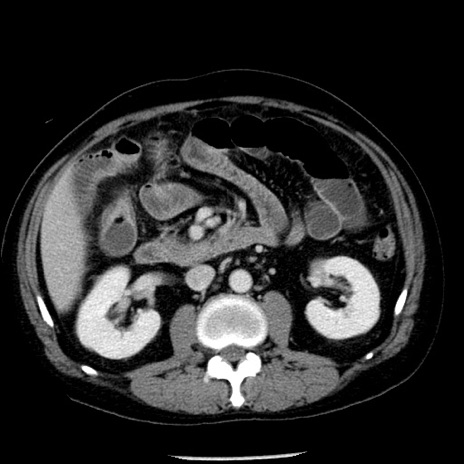

冠状断像

【症例】40歳代男性

【現病歴】2日前から胃痛あり。徐々に周期的な激痛に変化した。本日になっても激痛があるため受診。

【身体所見】意識清明、BT 38-39℃台あり、腹部:膨満、やや硬、右下腹部に圧痛あり。

【データ】WBC 8500、CRP 23.26